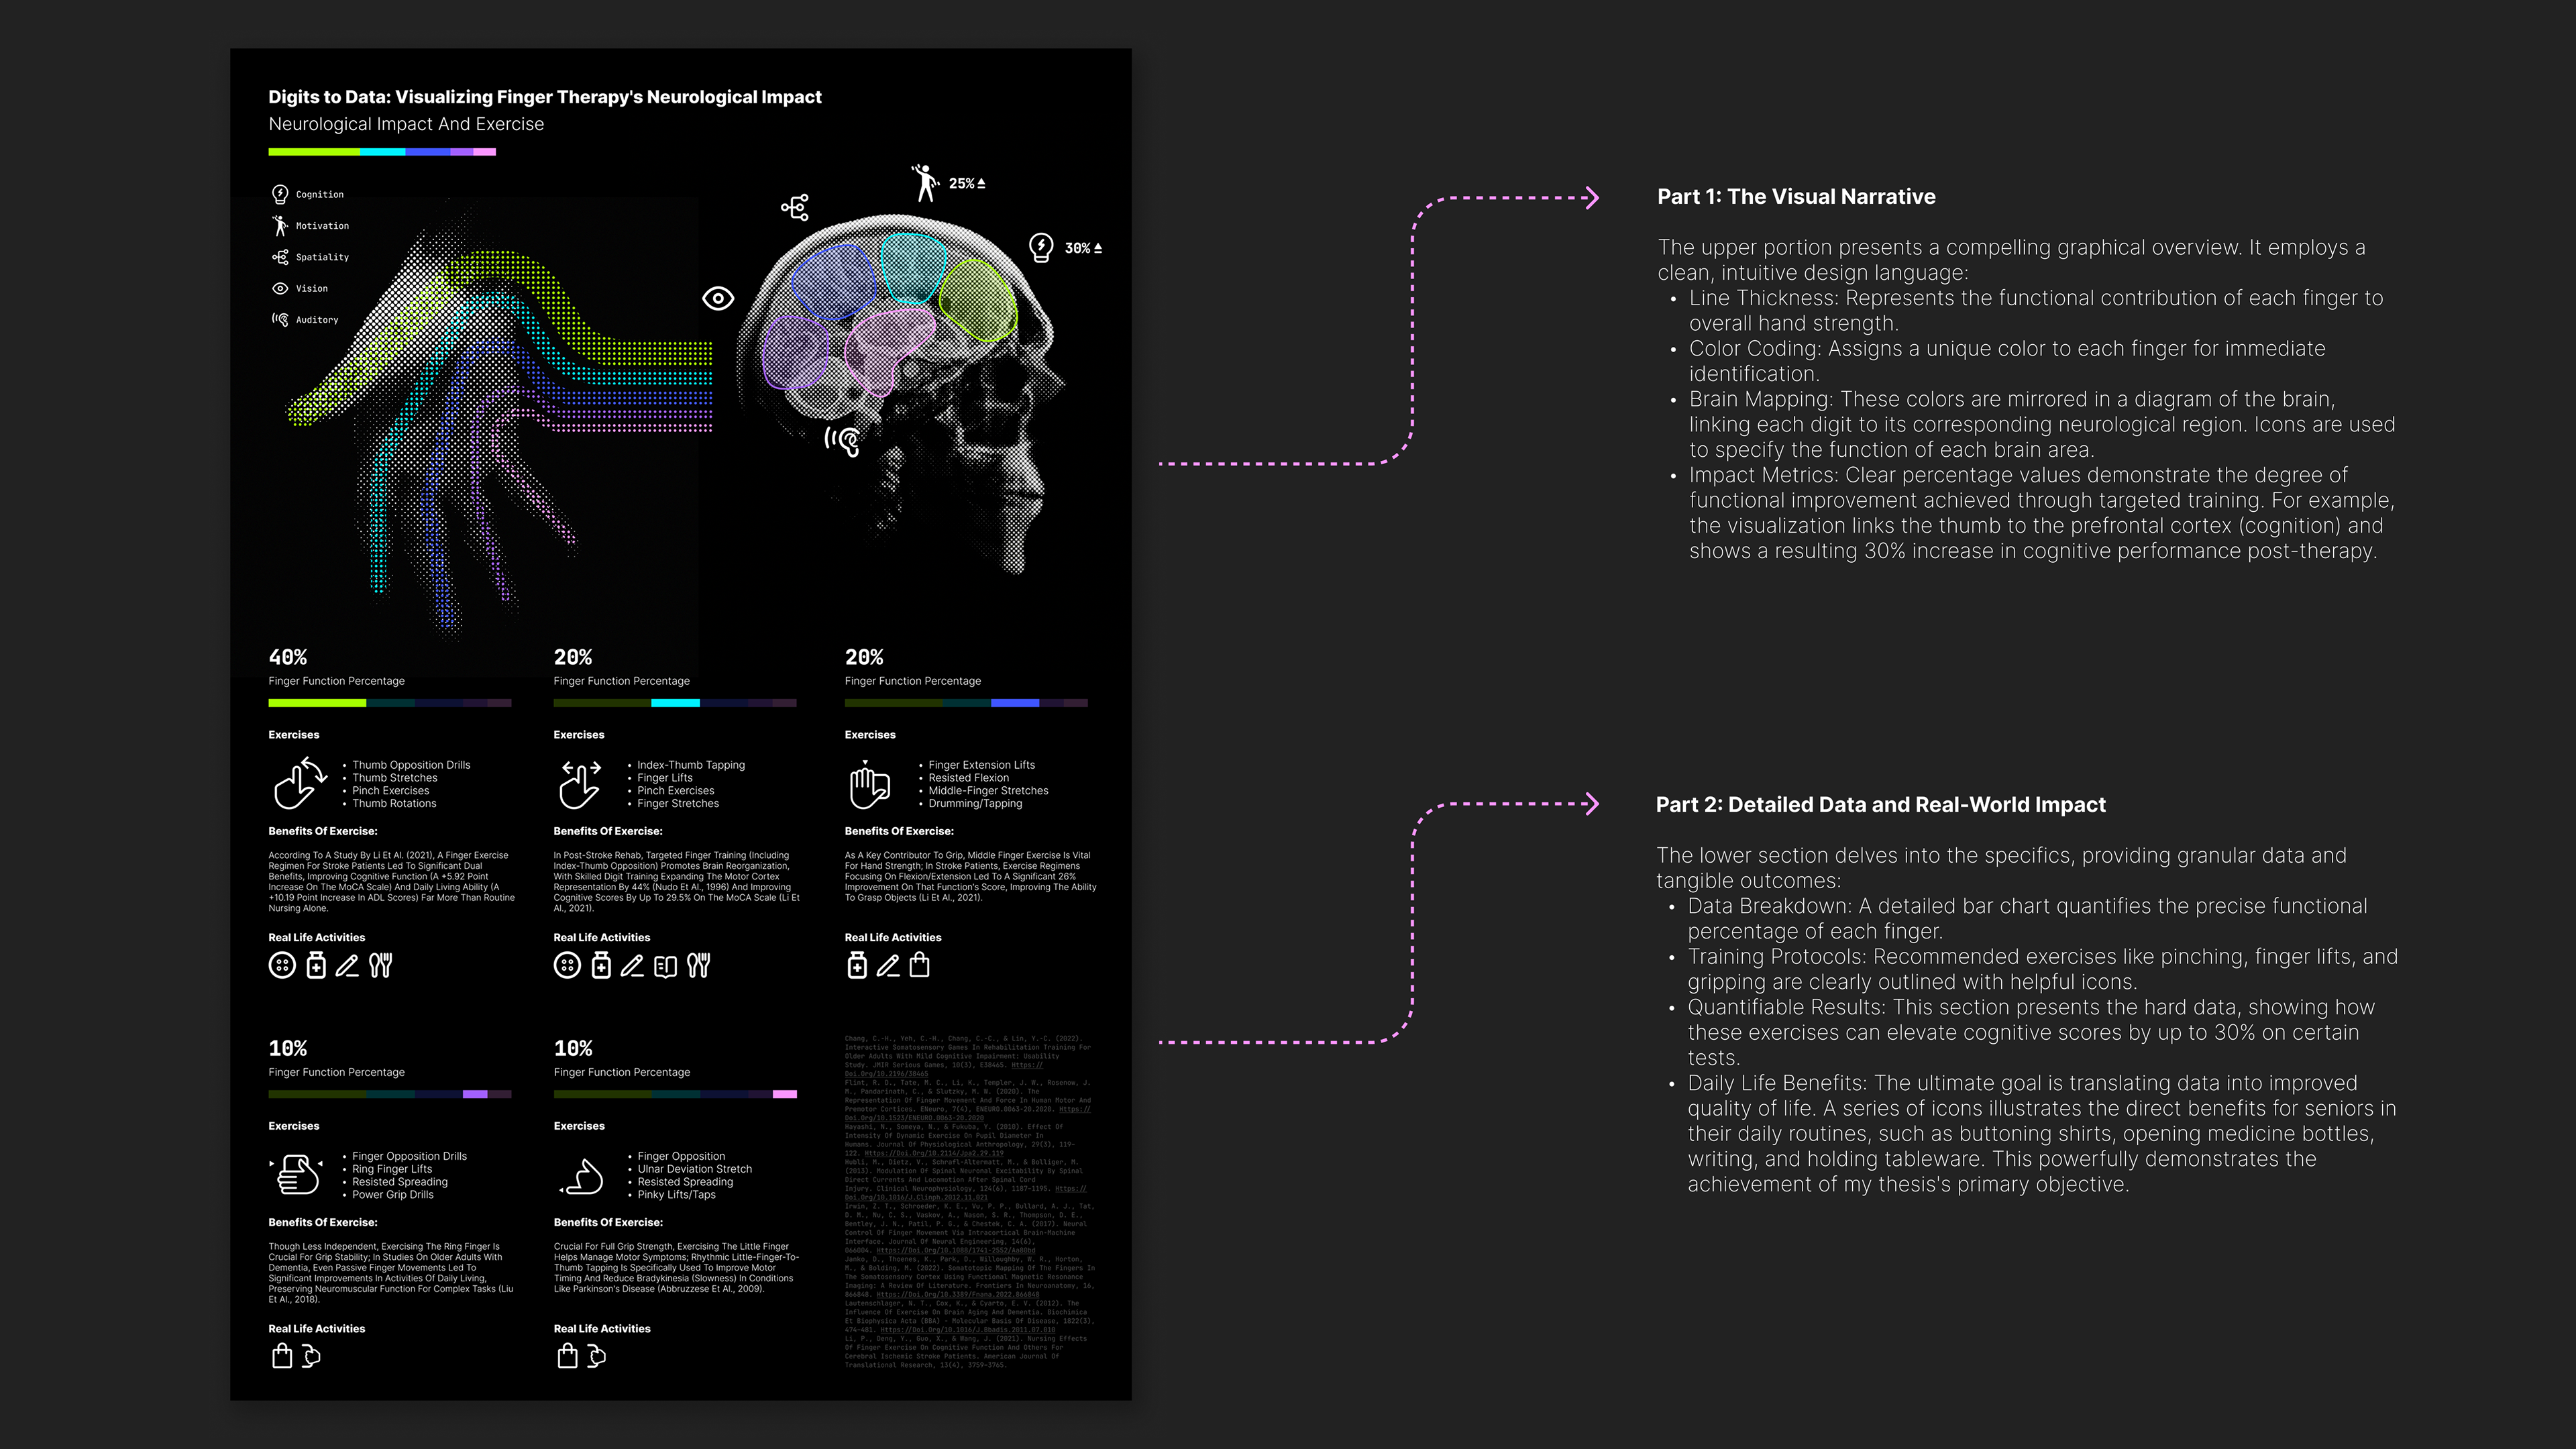

Visualizing Finger Therapy's Neurological Impact

A data visualization illustrating the impact of finger therapyon the nervous system.

Introduction to thesis research: "Human-Centered Design for Maintaining Senior Hand Grip Strength." This visualization conveys design concepts and research direction by clearly illustrating the profound impact of finger therapy on the nervous system.